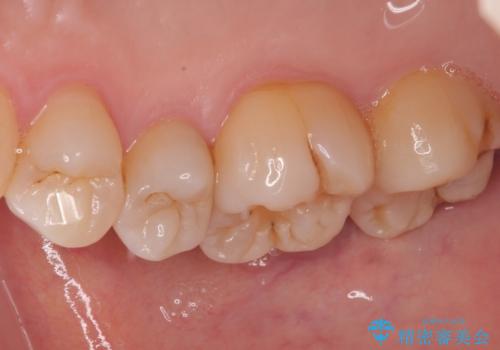

オールセラミッククラウンによる奥歯のむし歯治療

やはりむし歯は大きく、一部歯髄を切除することとなりましたが、その後は良好な経過をたどっています。